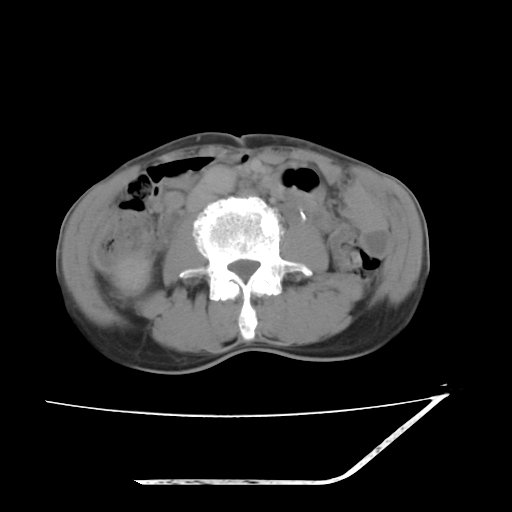

平扫

考虑右肾盂癌,肾动脉受侵,右肾功能减退,右肾盂输尿管积水,管壁增厚,考虑种植转移,应该把下面扫完的

支持右侧肾盂癌伴肾静脉瘤栓形成可能性大,右肾结石.肝右叶后段低密度影,不除外转移.

右肾盂旁ca并肾静脉瘤栓形成/肾功能降低。

右肾结石。

右肾盂癌,肾动脉受侵,右肾盂输尿管积水,管壁增厚,考虑种植转移

支持 右侧肾盂癌伴肾静脉瘤栓形成可能性大,右肾结石;肝右叶后段低密度影,不除外转移。

1.右侧肾盂癌伴肾盂积水。

2.肾脏功能减退,原因有:(1)肾动脉受侵。(2)肾静脉受侵(3)肾积水,等。本例,肾动脉显影较好,但受压明显;肾静脉无明显显示,受压或静脉癌栓,下腔静脉腔内未见明显充盈缺损。

3.右侧上段输尿管扩张,原因:(1)积水所致;(2)种植。